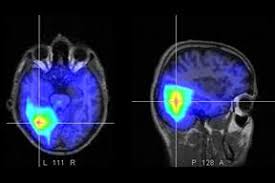

Un accidente cerebrovascular, infarto cerebral o ataque cerebrovascular (ACV) se produce cuando se tapa u obstruye una arteria o cuando se rompe un vaso. Ante esta situación, la parte del cerebro afectada no recibe el oxígeno necesario y comienzan a morirse neuronas.

Un accidente cerebro vascular, infarto cerebral o ataque cerebro vascular (ACV) se produce cuando se tapa u obstruye una arteria o cuando se rompe un vaso. Ante esta situación, la parte del cerebro afectada no recibe el oxígeno necesario y comienzan a morirse neuronas.

Reconocer los síntomas del ACV es fundamental, ya que cada minuto sin tratamiento implica la muerte de 1.900.000 neuronas y las conexiones entre ellas, lo que ocasiona más secuelas para la persona que lo sufre.

Los síntomas más sugestivos son aquellos que aparecen de manera repentina y sin causa aparente. Entre ellos, la pérdida de la fuerza o la disminución de sensibilidad de un lado del cuerpo – que caiga un vaso que sostenía con la mano, por ejemplo. Otra señal de alerta es la alteración de la articulación de las palabras o le aparición de trastornos del lenguaje o problemas con la vista, ya sea un recorte del campo visual o “ver doble”. También son llamadas de atención la alteración del equilibrio, la cefalea intensa y/o pérdida de conocimiento.